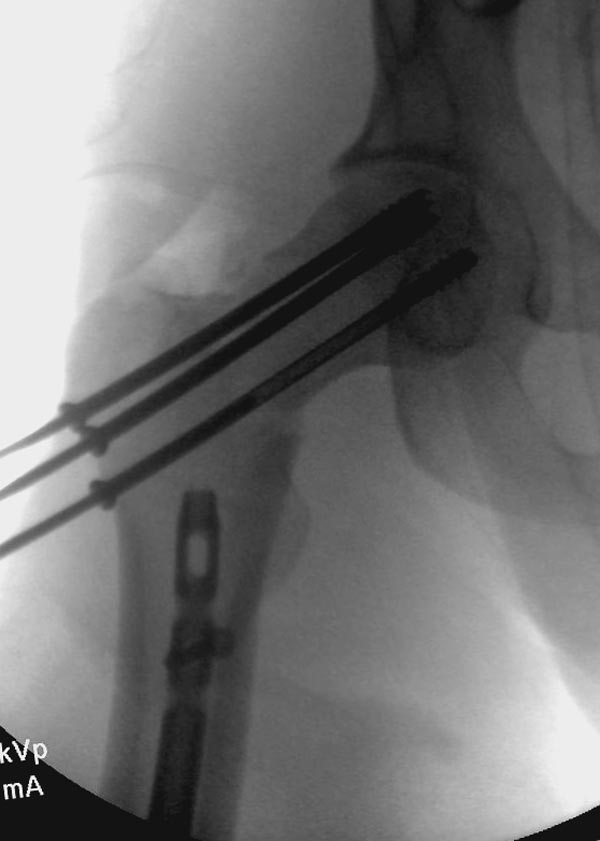

несращения! По истечению 4 месяцев появились признаки варусной

деформации. На СТ срезах несращение шейки и бедра. Риминг, замена на

более толстый гвоздь и вальгусная остеотомия.